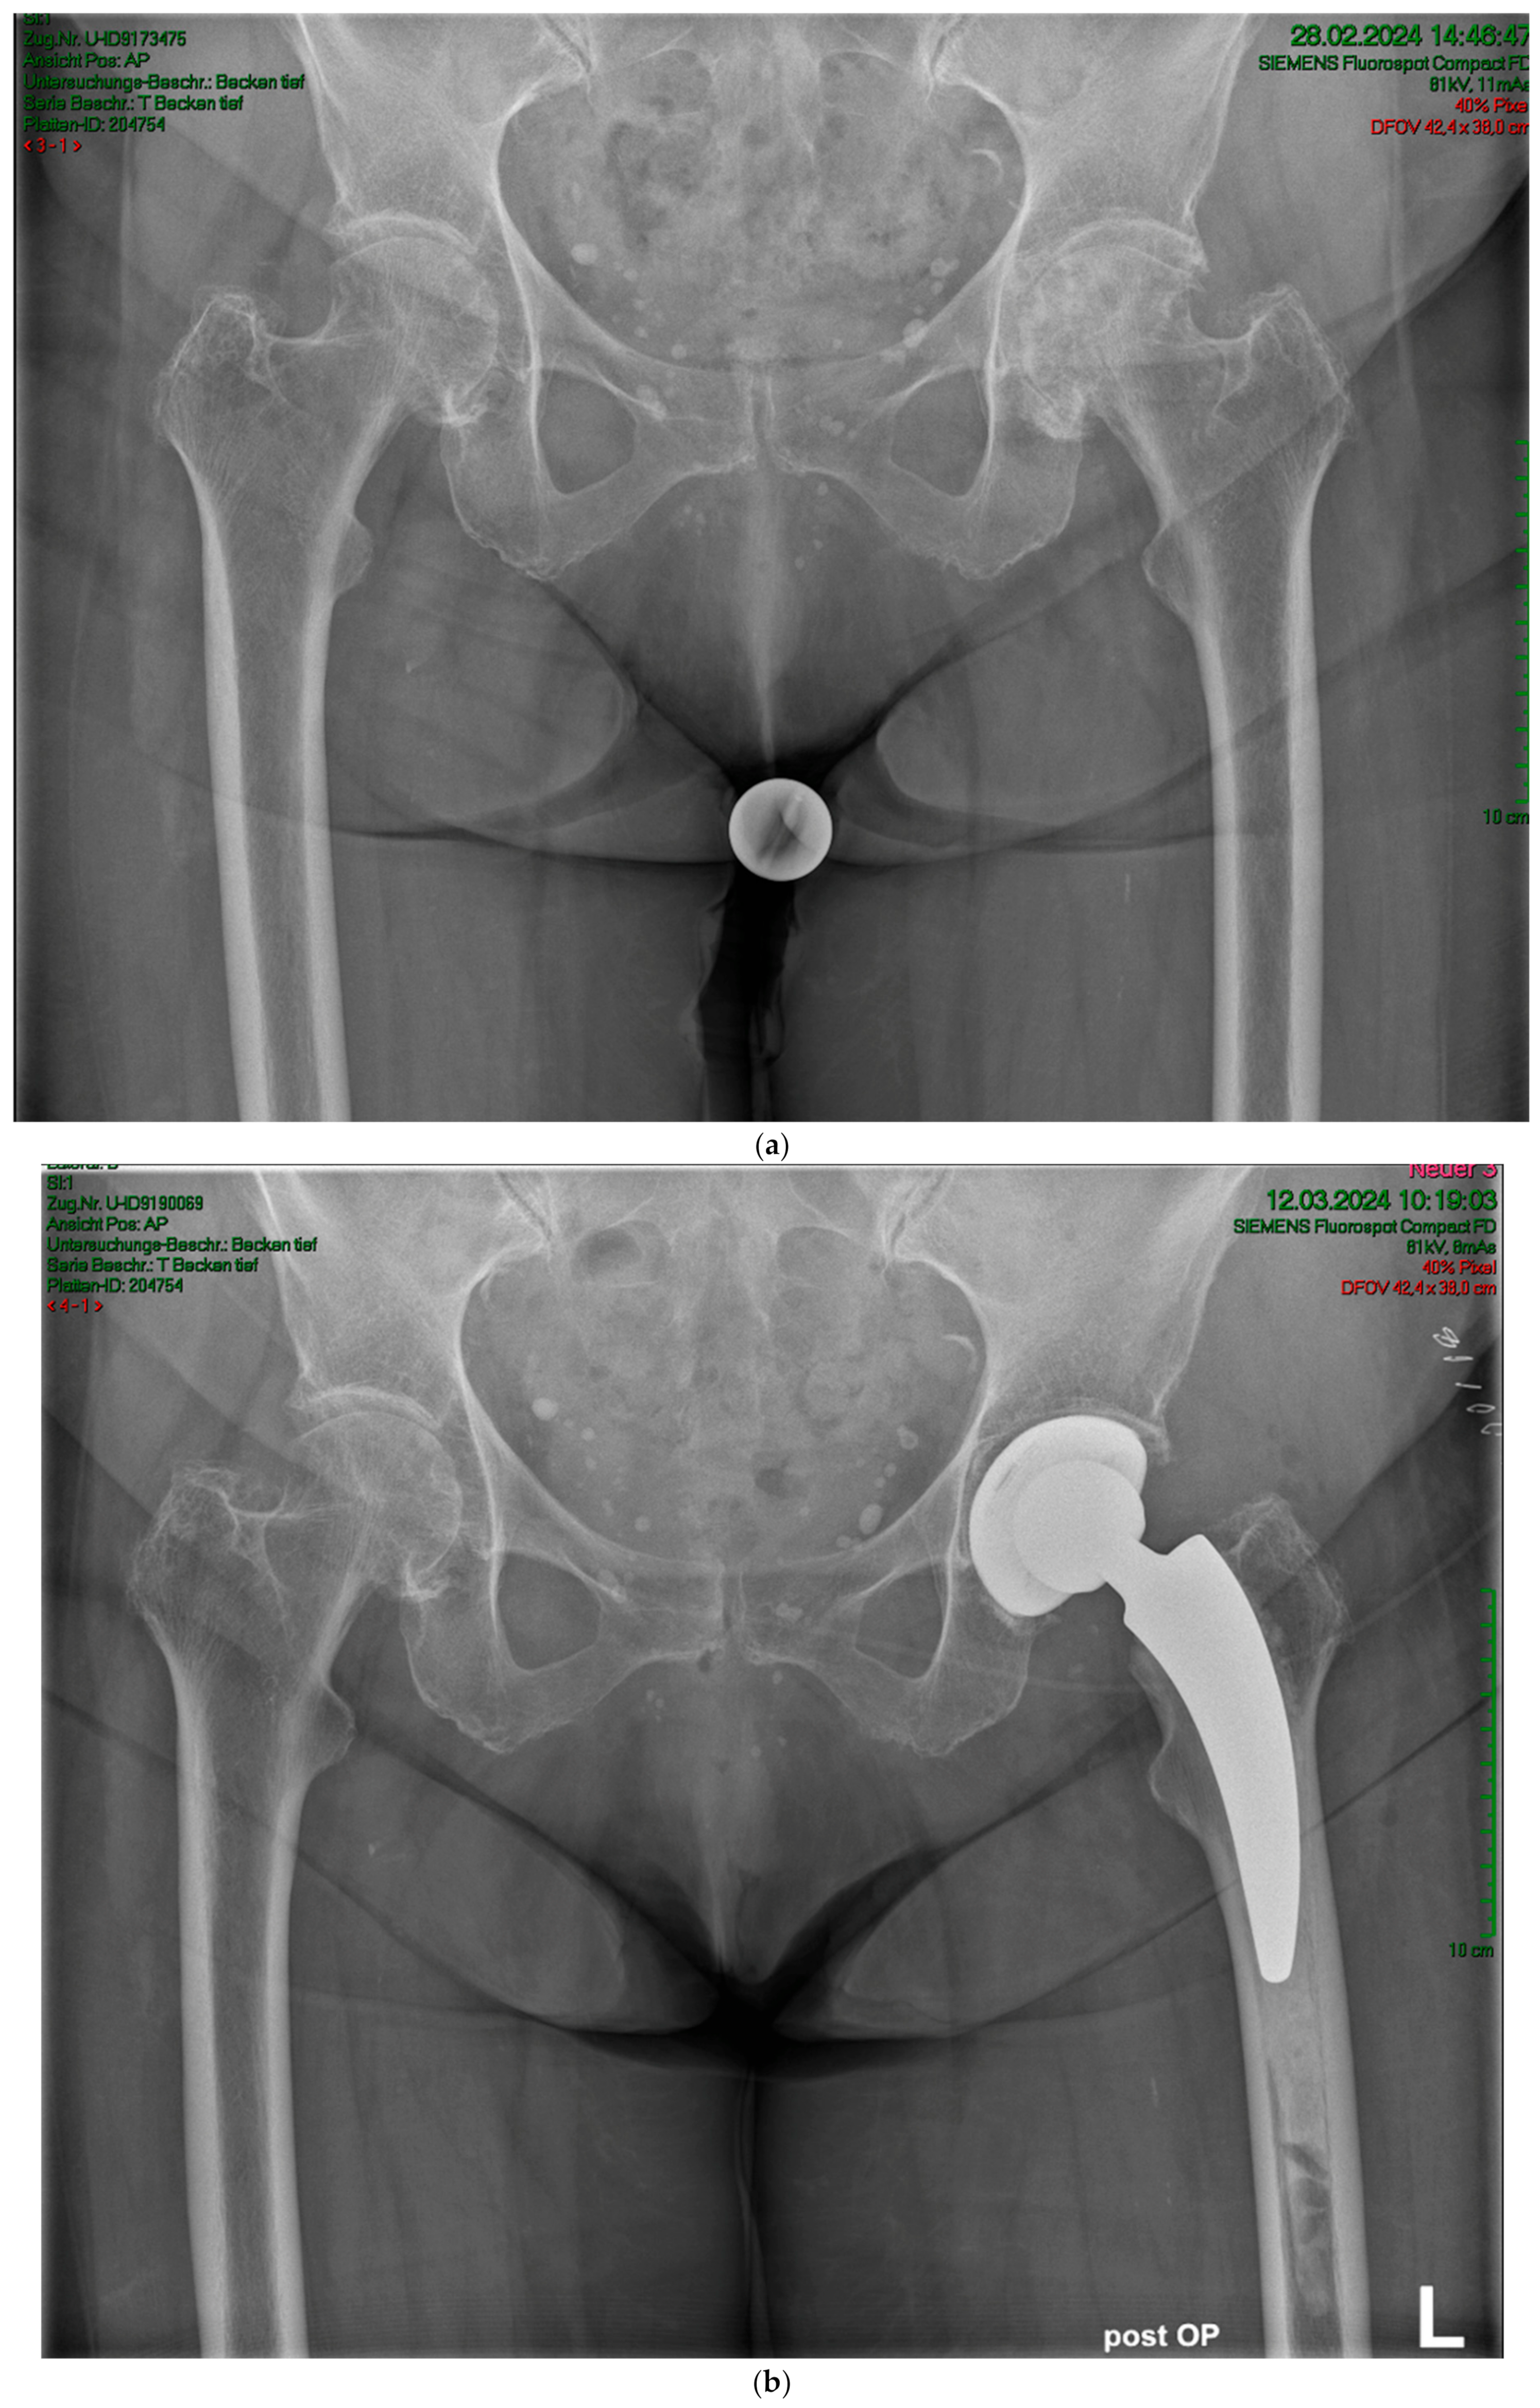

2. Materials and Methods